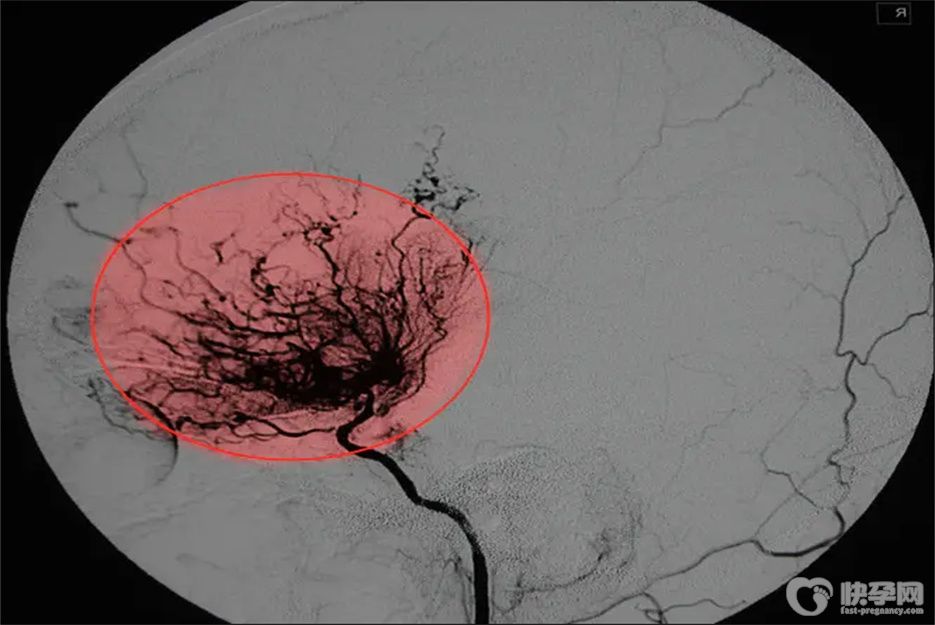

烟雾病是一种病因不明的脑血管疾病,以双侧颈内动脉末端、大脑前动脉和大脑中动脉始端慢性进行性狭窄或闭塞为特征,继发于颅底异常血管网形成。那么,烟雾病患者能做试管婴儿吗?

烟雾病患者是可以做试管婴儿的,烟雾病主要是颅底血管的畸形,是属于一种先天性疾病,是颈内动脉虹吸段或大脑前动脉、大脑中动脉起始段的狭窄和闭塞,会影响正常的脑供血,容易导致脑缺血和脑出血。在治疗病情稳定后是可以做试管婴儿的,虽然怀孕有一定的影响和风险,但并不意味着怀孕后病情会加重。只要在孕期注意控制血压,生活规律,就可以预防脑出血和脑梗塞。